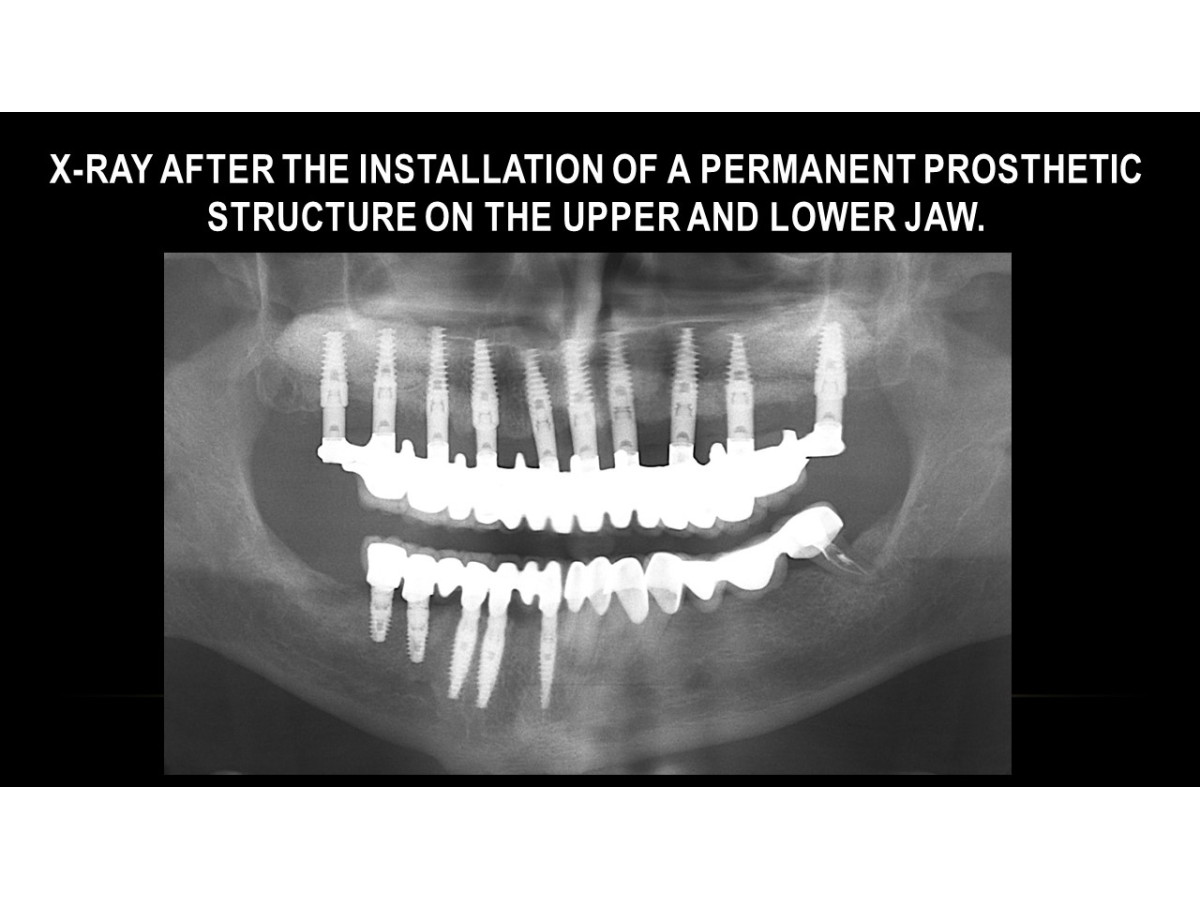

Clinical case: Treatment of complications of dental implantation using Unique dental implants

Dentist: DDS PhD prof. Ilia Mushayev/Sidhedent (Israel)

Clinical case, dental implantation